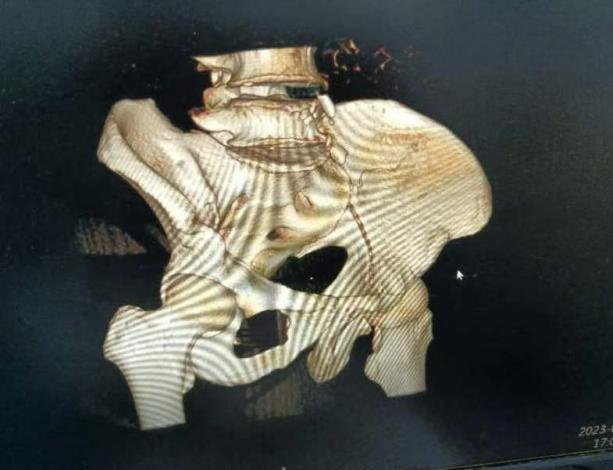

术前CT